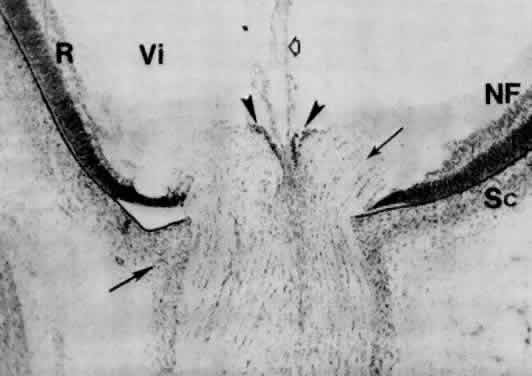

Light and scanning electron-microscopic studies reveal the anterior chamber angle of the human eye to have a continuous endothelial lining during the third and fourth months (Figs. 17 and 18). The tissues in the angle later differentiate into a loose reticulum with large enclosed spaces near the iris and ciliary body; outside of this trabecular tissue, a tighter aggregation of cells is oriented toward the sclera.111–115 With the growth of surrounding structures, Schlemm's canal comes to lie at the level of the apex of the angle. Descemet's membrane and the corneal endothelium still cover a portion of the trabecular meshwork, but the endothelial lining of the chamber has become discontinuous (Figs. 19 and 20). The loose reticular tissue of the earlier stages now occurs only in the deepest part of the angle, where it has large intercellular spaces (see Figs. 17C and 20).

Fig. 19. Angle at 7 months (approximately 225 mm). Apex of the wedge-shaped trabecular meshwork (Tr) is not in the illustration. The corneal endothelium (En) extends over one third of the trabecular lamellae. The loose tissue in the angle recess is isolated from the anterior chamber (AC) by processes of the reticular and mesenchymal cells (hollow arrows). There are large clefts (*), some of which are confluent, in the angle tissue. The angle recess extends beyond the level of the middle of the trabecular meshwork, and the immature Schlemm's canal (circled) is somewhat behind it. Ir, immature iris; Sc, sclera. (Smelser GK, Ozanics V: The development of the trabecular meshwork in primate eyes. Am J Ophthalmol 71:366, 1971.)

Fig. 20. The angle in a fetus late in the ninth month (at approximately 37 weeks) extends somewhat beyond the posterior part of the trabecular meshwork, which has its apex at the termination of the corneal endothelium (En). The scleral spur (arrow) and the canal of Schlemm (arrowhead) are in front of the angle. Loose tissue in the angle is indicated by the hollow arrow. AC, anterior chamber; CM, ciliary muscle; cp, ciliary processes; C, cornea; Ir, iris; PC, posterior chamber; Sc, sclera.

Anterior chamber angle formation seems to occur through a combination of processes. Differential growth of the vascular tunic results in posterior movement of the iris and ciliary body relative to the trabecular meshwork and exposure of the outflow pathways.116 In addition, there is gradual cellular rearrangement and mesenchymal atrophy, as well as enlargement of numerous large spaces, until they become confluent with the anterior chamber.111

Following initial separation into corneoscleral and iridociliary trabecular regions at 15 weeks' gestation, the corneal trabeculae enlarge and there is regression of the corneal endothelium covering the angle recess. The discontinuity of the cellular layer covering the angle and the many lacunae present in late gestation may be correlated with the normal development of an increase in the outflow facility of aqueous humor. Outflow facility of fetal eyes under constant pressure reveals progressive increase with the age of the fetus (0.09 μl/min/mmHg before 7 months to 0.3 μl/min/mmHg at 8 months).117,118 It may be speculated that, if the splitting and rebuilding of the endothelial membrane lining of the early iridocorneal angle is arrested, a block to normal outflow may result. Persistence of the endothelial (Barkan's) membrane has been postulated to be of significance in the pathogenesis of congenital glaucoma.